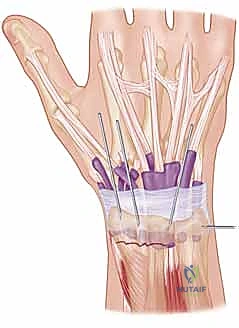

4. إدخال الأسلاك المعدنية (Pinning)

باستخدام مثقاب جراحي كهربائي دقيق، يقوم الدكتور هطيف بإدخال السلك المعدني الأول عبر الجلد، مروراً بالعظم السليم، ثم يعبر خط الكسر ليصل إلى الشظية المكسورة ويثبتها.

هناك عدة تقنيات هندسية لإدخال الأسلاك، أشهرها:

* التثبيت المتقاطع (Cross-Pinning): إدخال سلكين من زوايا مختلفة ليتقاطعا داخل العظم، مما يوفر ثباتاً دورانياً ممتازاً.

* تقنية كابانجي (Kapandji Technique): إدخال الأسلاك مباشرة في خط الكسر واستخدامها كرافعات لرفع العظم المنخسف ثم دفعها في العظم المقابل لتثبيته. يتميز الدكتور هطيف ببراعة فائقة في تطبيق هذه التقنية المعقدة.